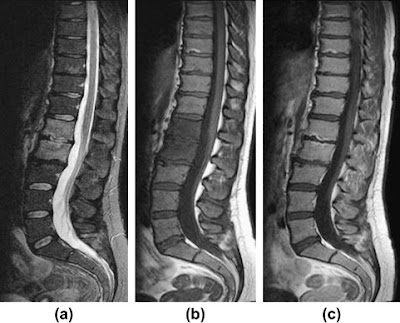

| T1 sagittal image of the lumbar spine demonstrates a band of decreased signal at the superior L3 endplate and inferior L2 endplate... the decreased signal is an indication of edema. |